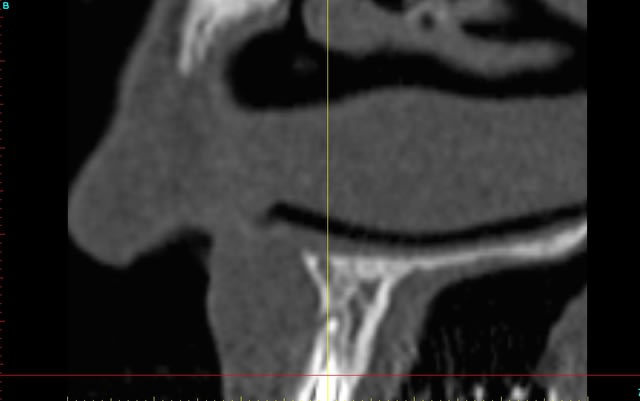

le scan n'est pas terrible, mais suffisant pour voir que 22 une fois extraite, ne va pas etre simple à implanter, par contre 11/21 avec un peu d'expansion...

Des lecross section21 jinha0 - Eugenol

Des lecross section sf6tbl - Eugenol

Des le cross section 12 vyz5ug - Eugenol

Des le cross section 22 w31w6b - Eugenol